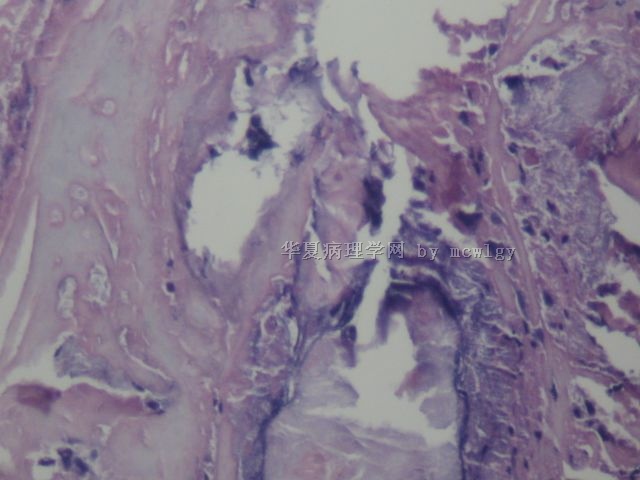

姓    名: ××× 性别:  男 年龄:  42

简要病史:  发现无痛肿物10天。

肉眼检查:  不整形3.5*3.5*2.5CM,红褐色,切面灰黄红褐色,质中.

再传几张图片。能否考虑滑膜瘤?

结节性筋膜炎不典型,可以描述性诊断,其内见滑膜细胞增生伴出血,好像还有些异物之类的东西